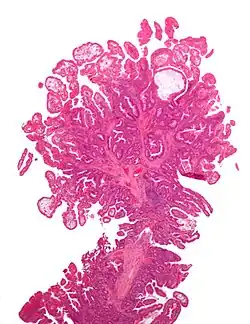

Tubular adenoma 2% at 1.5 cm[12] Low to high grade dysplasia[13] Over 75% of volume has tubular appearance.[14]

Tubulovillous adenoma 20% to 25%[15] 25–75% villous[14]

Villous adenoma 15%[16] to 40%[15] Over 75% villous[14]